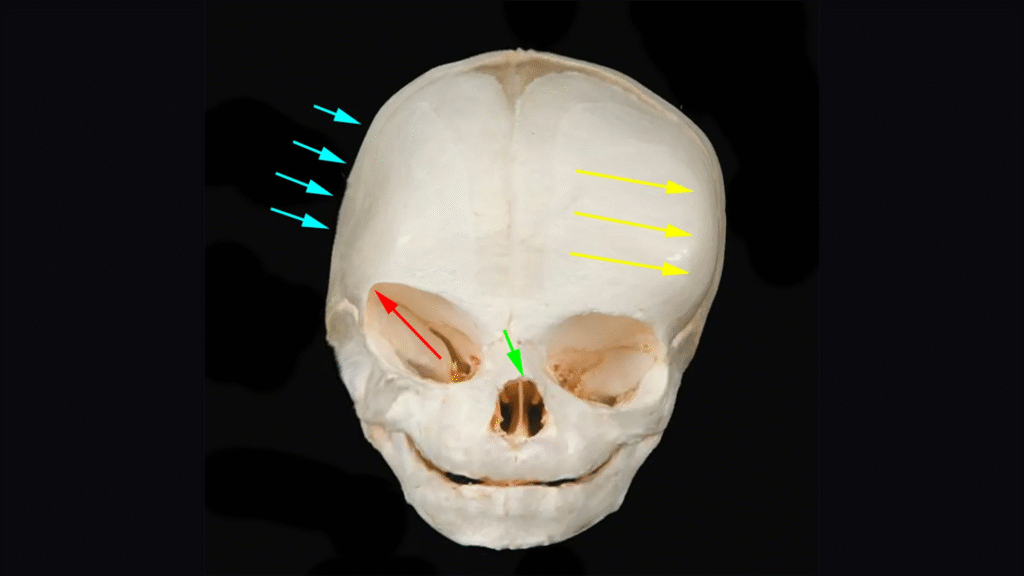

At El Paso Craniofacial Team, the primary treatment for craniosynostosis is surgery. First performed in the late 1800s, surgical approaches have continued to evolve and improve. The two main approaches are Calvarial Vault Remodel (CVR) and endoscopic-assisted surgery, with each tailored to the child’s age, the affected suture, and the severity of the condition.